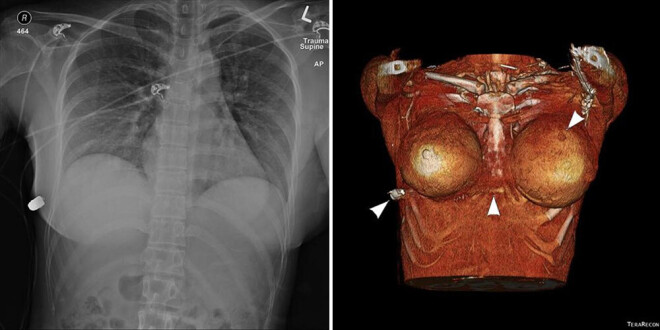

Silikona krūtis glābj sievietes dzīvību

30 gadus veca Kanādas iedzīvotāja pastāstīja, ka, ejot pa Toronto ielām, pēkšņi ķermenī sajuta dedzinošu sajūtu un sāpes, bet pēc tam viņa ieraudzīja asinis. Meitene tika nogādāta Misisogas slimnīcā, kur ķirurgi no viņas krūts izņēma lodi, kas tika nosūtīta tālākai ekspertīzei.

Neskatoties uz to, ka lode trāpīja krūšu rajona kreisajā pusē, sieviete palika dzīva un tika cauri vien ar lauzu ribu. Mediķi pieļauj, ka sievieti no nāves paglābis krūšu implants, kas mainījis sirds virzienā lidojušās lodes trajektoriju.

Vēlāk izrādījās, ka uzbrukuma laikā cietis arī otrs implants, tāpēc sievietei nācās atvadīties no kuplajām krūtīm. Par pārsteidzošo gadījumu vēsta "SAGE Journal".